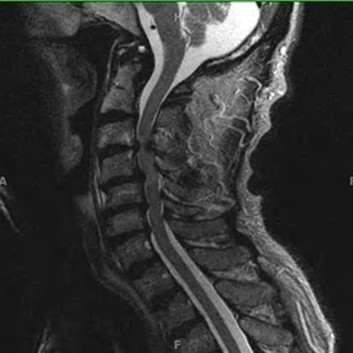

급성 디스크 손상 및 디스크 탈출증

허리 디스크에 의한 급성 통증 발생 시에도 심부신경 주사치료를 통해 효과적으로 통증을 조절 할 수 있습니다. 갑작스런 자극에 의한 신경의 통각 과민을 예방하고 붓고 파열 된 디스크의 크기를 줄임으로써 수술 없이 안전하게 치료가 가능합니다. 효과적인 치료를 위해 반복해서 치료 해야 합니다. 심각한 디스크의 파열은 수술이 필요 할 수도 있습니다.